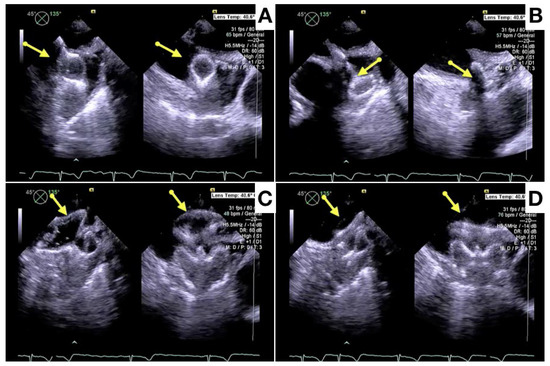

- Berti, S.; Pastormerlo, L.E.; Santoro, G.; Brscic, E.; Montorfano, M.; Vignali, L.; Danna, P.; Tondo, C.; Rezzaghi, M.; D’Amico, G.; et al. Intracardiac Versus Transesophageal Echocardiographic Guidance for Left Atrial Appendage Occlusion: The LAAO Italian Multicenter Registry. JACC Cardiovasc. Interv. 2018, 11, 1086–1092. [Google Scholar] [CrossRef] [PubMed]

- Nielsen-Kudsk, J.E.; Berti, S.; De Backer, O.; Aguirre, D.; Fassini, G.; Cruz-Gonzalez, I.; Grassi, G.; Tondo, C. Use of Intracardiac Compared With Transesophageal Echocardiography for Left Atrial Appendage Occlusion in the Amulet Observational Study. JACC Cardiovasc. Interv. 2019, 12, 1030–1039. [Google Scholar] [CrossRef] [PubMed]

- Alkhouli, M.; Chaker, Z.; Alqahtani, F.; Raslan, S.; Raybuck, B. Outcomes of Routine Intracardiac Echocardiography to Guide Left Atrial Appendage Occlusion. JACC Clin. Electrophysiol. 2020, 6, 393–400. [Google Scholar] [CrossRef]

- Ribeiro, J.M.; Teixeira, R.; Puga, L.; Costa, M.; Gonçalves, L. Comparison of intracardiac and transoesophageal echocardiography for guidance of percutaneous left atrial appendage occlusion: A meta-analysis. Echocardiography 2019, 36, 1330–1337. [Google Scholar] [CrossRef] [PubMed]

- Nielsen-Kudsk, J.E.; Berti, S.; Caprioglio, F.; Ronco, F.; Arzamendi, D.; Betts, T.; Tondo, C.; Christen, T.; Allocco, D.J. Intracardiac Echocardiography to Guide Watchman FLX Implantation: The ICE LAA Study. JACC Cardiovasc. Interv. 2023, 16, 643–651. [Google Scholar] [CrossRef]